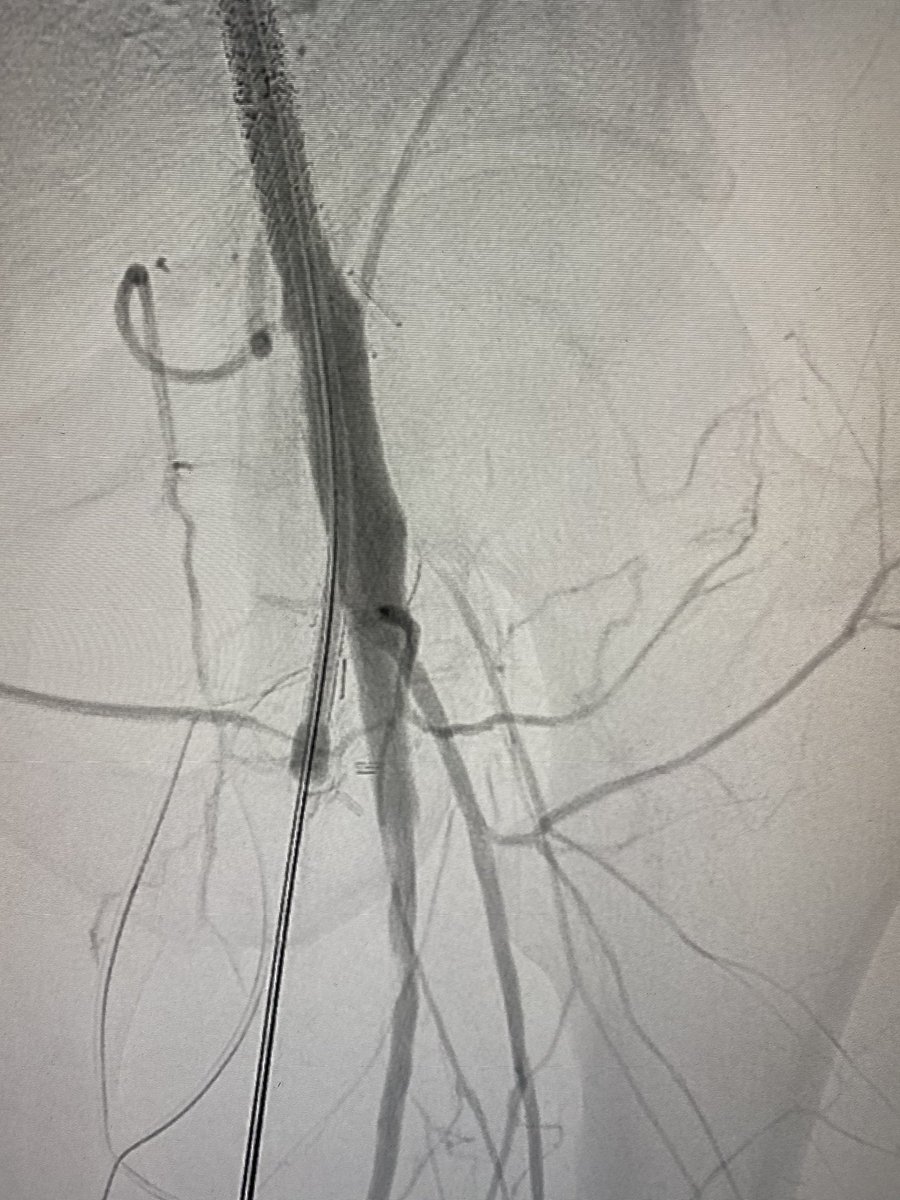

Dan Fremed@DanFremed·

@mattsmeds Still a stubborn up-and-overist- 200 shaft length rx ultraverse balloons have been helpful

Matthew Smeds

Matthew Smeds@mattsmeds·

Anyone doing much pedal arch balloon angioplasty out there? Tips/tricks?